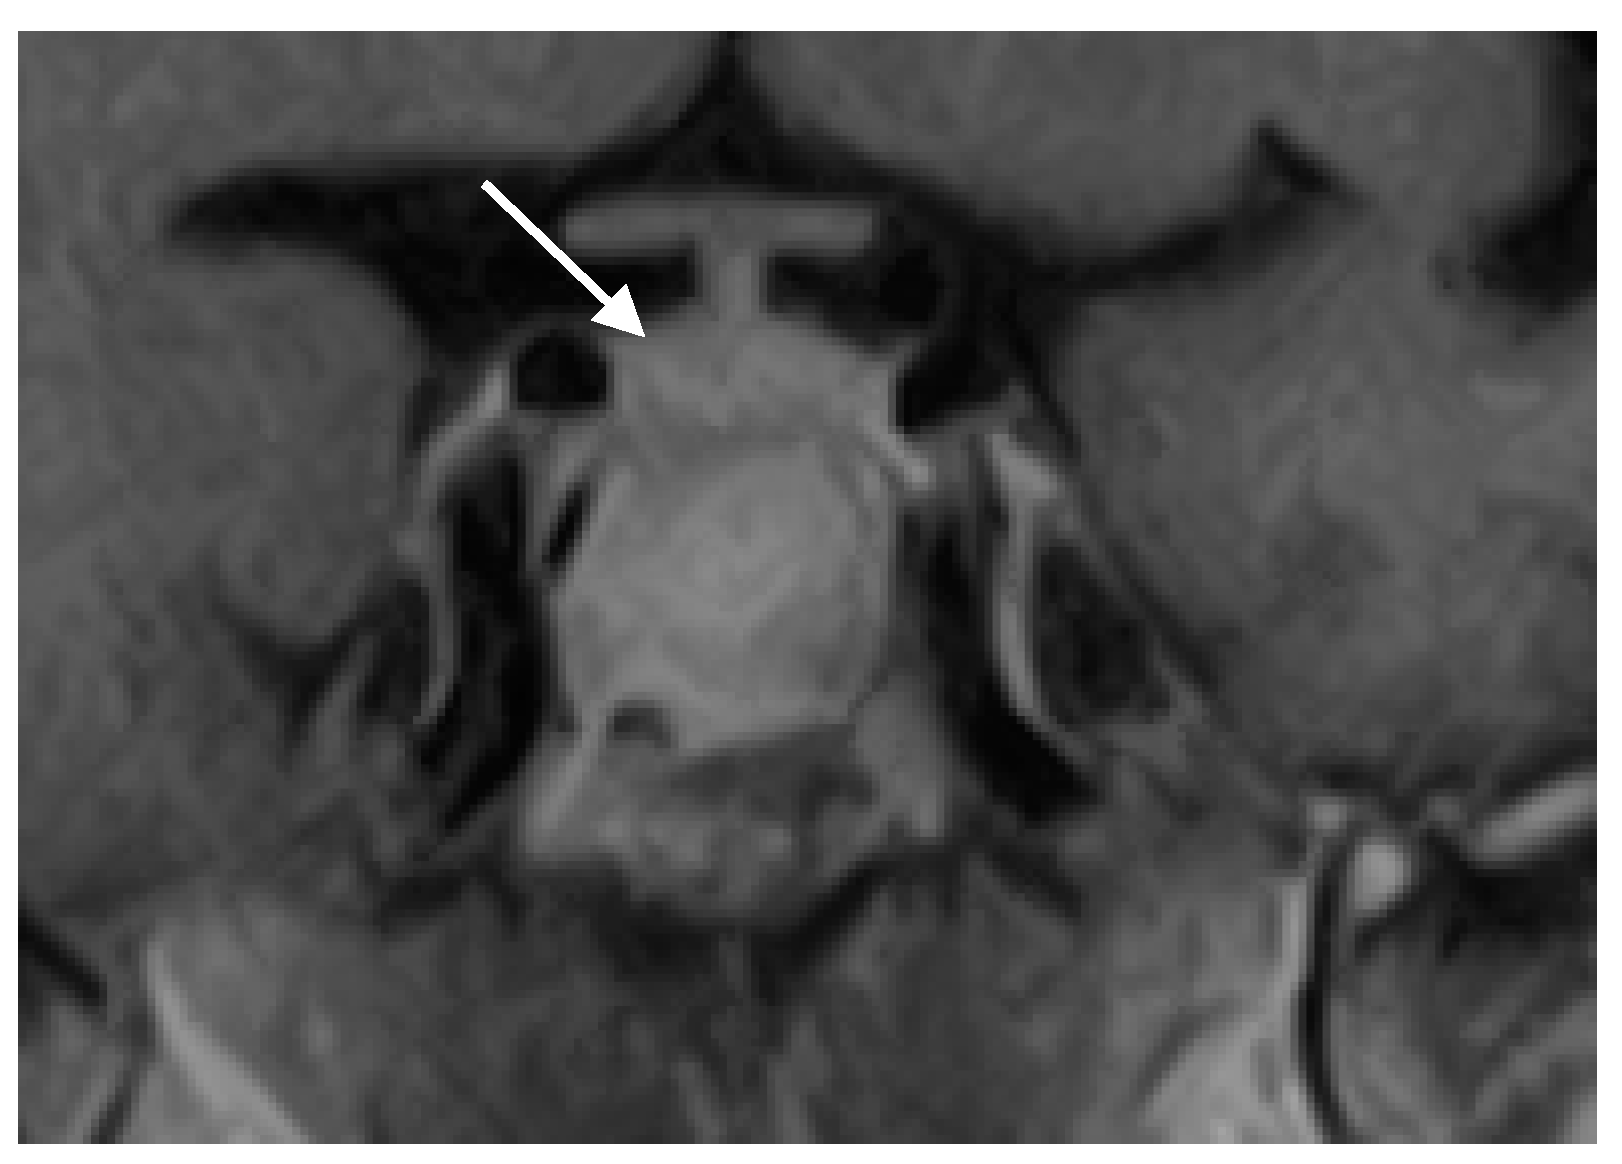

3.1. Case Presentation

3.3. Surgical and Pathological Findings